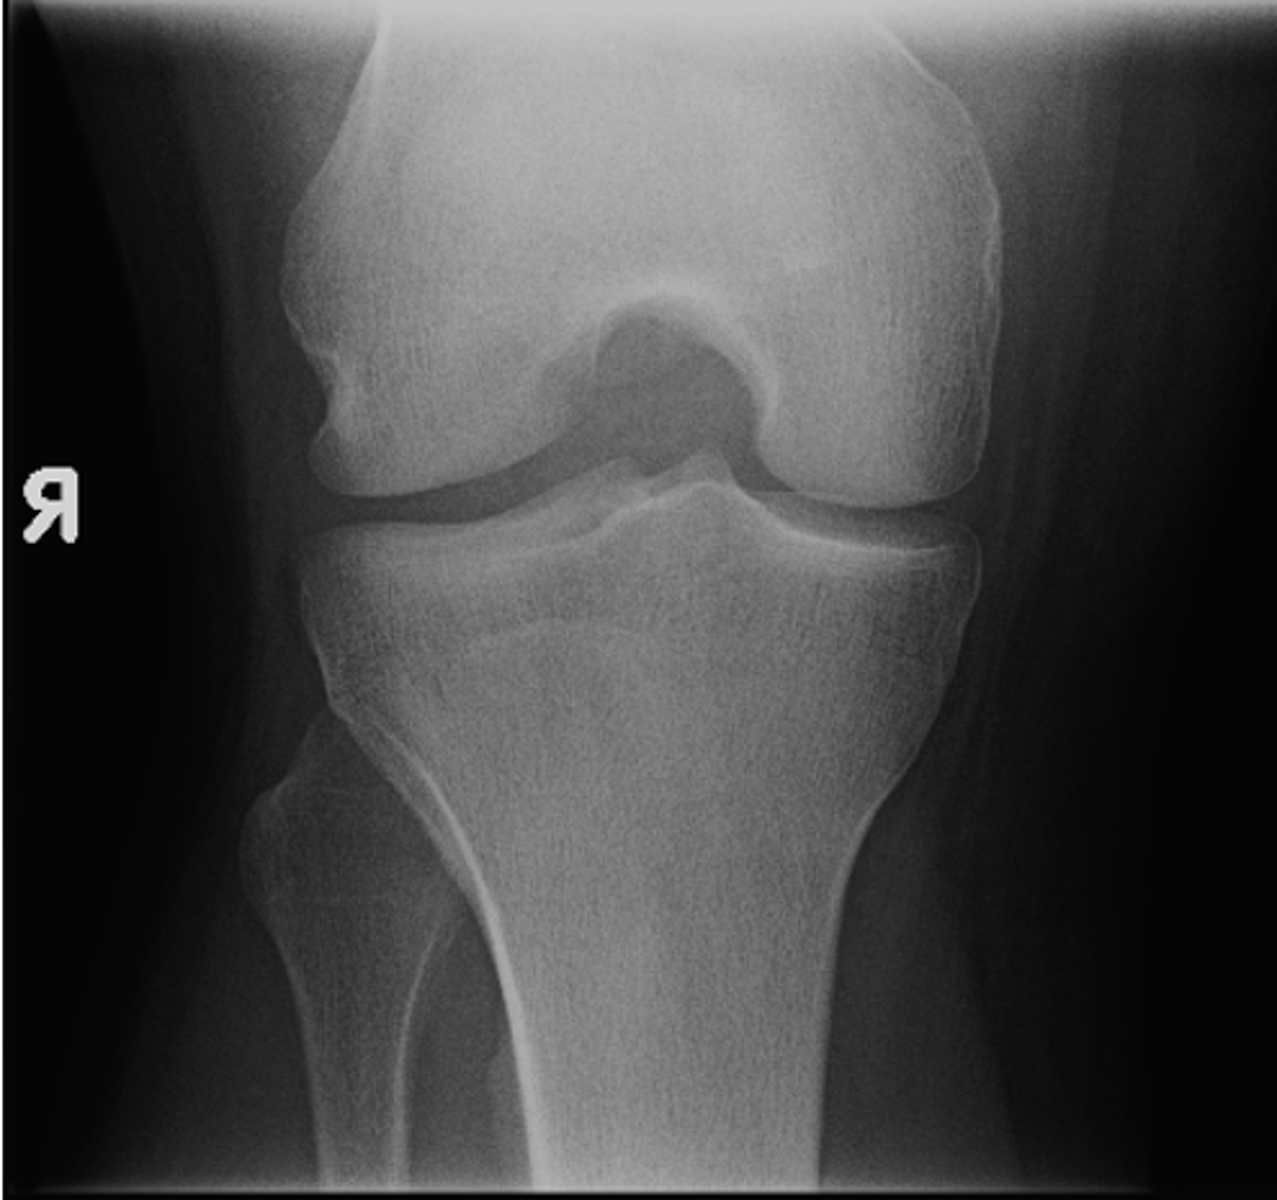

- AP knee

- Lateral knee

- Tunnel (intercondylar) knee

State the standard knee projections

AP knee

ID standard knee projection

<p>ID standard knee projection</p>